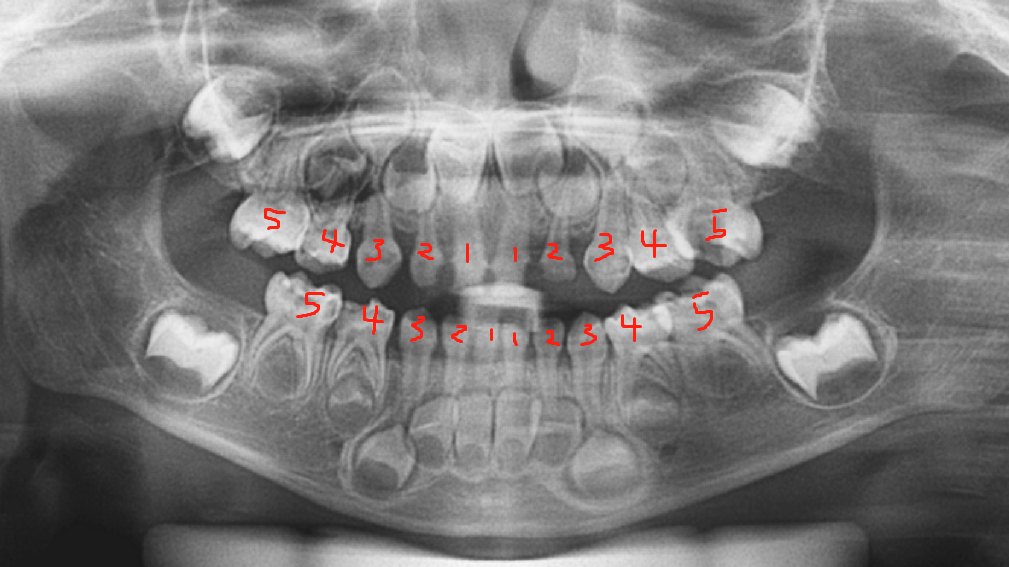

乳牙两岁半长齐,共20颗。(下图为三岁全景片:左右各五颗,上下各十颗)